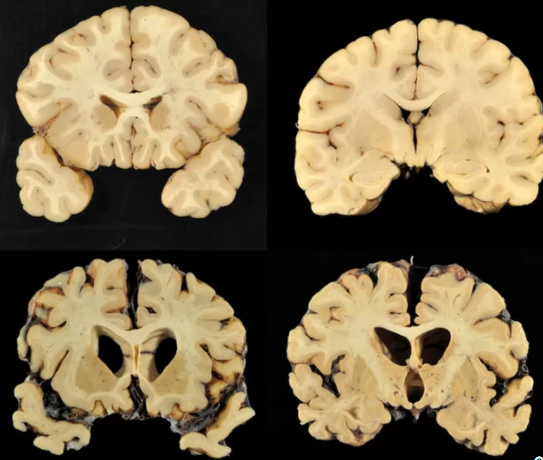

미국의 한 연구에 의하면 사망한 200명(111명은 국제 미식축구 리그에 속한 회원) 중 90%에 육박한 회원들은 뇌 질병 – 외상뇌병(chronic traumatic encephalopathy CTE)을 앓고 있다.

7월 25일, JAMA저널에서의 발표에 의하면 연구자들은 외상뇌병(CTE)의 증거를 202개의 뇌중 177개에서 발견했다. 즉 87%에 육박하다. NFL의 선수의 뇌에는 111명 중 110명, 99퍼센트 이상이 CTE를 갖고 있다. (여기서의 1명은 자신의 뇌를 미식축구 연구, 대학, 고등학교에 기증한다고 했다)